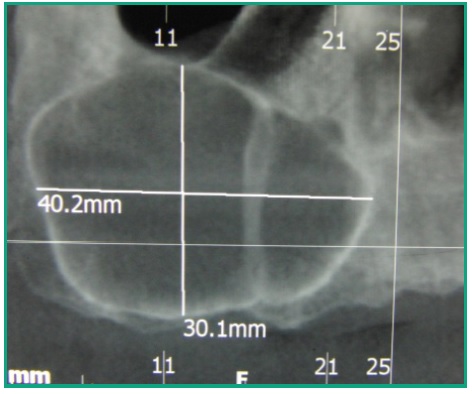

A efectos del diagnóstico y plan de tratamiento se indica una Tomografía Computada (TC), examen realizado a través de adquisición de haz cónico único de rayos X, donde se corroboran las medidas de la lesión de 40.2 mm. en sentido ántero posterior por 30.1mm en sentido vertical. En todos los cortes tomográficos se observa que el seno maxilar derecho está ocupado por una lesión, con un tabicamiento a la altura del 13, que no deforma la pared nasal del seno maxilar (Figs. 4, 5).